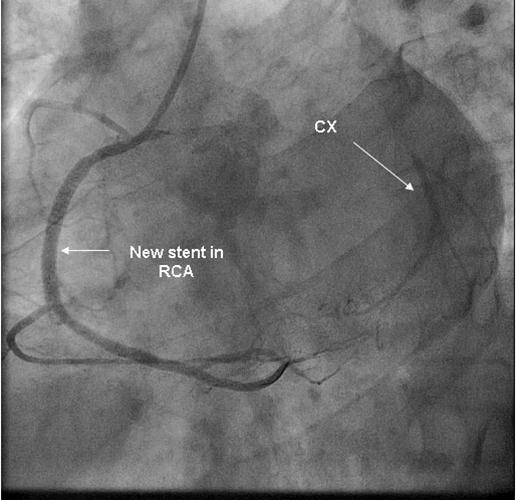

Coronary angiography was again performed. On injections into the left system, collaterals to the distal RCA were demonstrated (figure 1), arising from the left circumflex coronary artery (CX). Injections into the RCA demonstrated tight in-stent restenosis, (figure 2) and a drug eluting stent was successfully implanted. After the angioplasty, injections into the RCA were seen to retrogradely fill the CX (figure 3). The suspicion arose that maybe the left coronary artery had been inadvertently damaged during angiography, so the left coronary was again cannulated and injections performed, demonstrating entirely normal left main and CX arteries. However, the collateral flow that had previously been demonstrated from the CX to the RCA was no longer apparent. On review of the previous angiogram, it was noted that the RCA retrogradely filled the CX despite the original significant stenosis (figure 4). In essence, it became apparent that the bidirectional filling of the RCA from the CX and vice versa was in fact a direct continuity between the vessels and not collaterals, as free flow was noted from the RCA to the CX even when both arteries were completely patent.

Figure 3.New stent in RCA with retrograde filling of CX